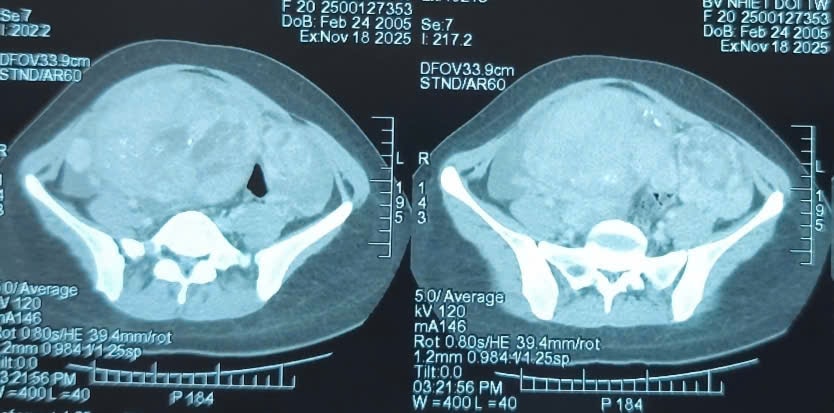

Bác sĩ sững người khi thấy khối u gần 3 kg chiếm trọn bụng cô gái 20 tuổi

(CLO) Bệnh nhân Đ.T.V. (20 tuổi, Hưng Yên) từng phẫu thuật lấy khối máu tụ và ghép xương sọ tại bệnh viện tuyến tỉnh sau chấn thương sọ não do tai nạn giao thông tháng 8/2025.